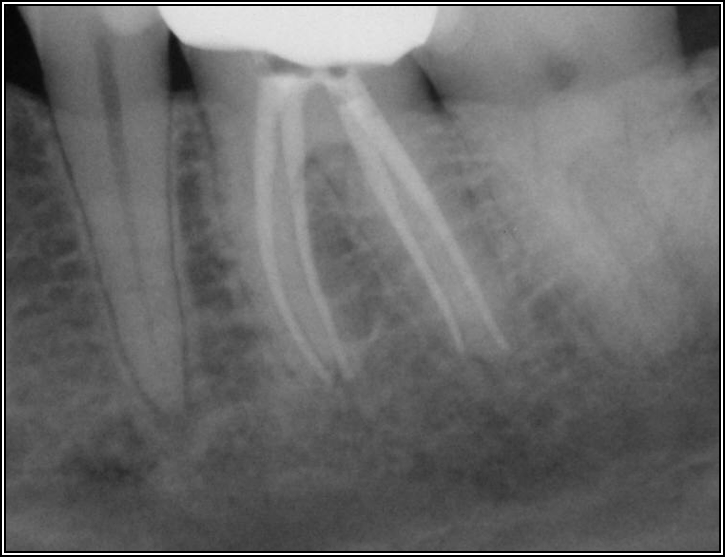

Figure 13 shows an example where there was likely a good root canal that was absorbed. The way to avoid this type of problem is that the person who does the root canal should do the post. This is not always possible, and some general dentists like to do the restorative work themselves, but the advantage of having the same person do both is that the person is familiar with the curve of that canal. That clinician also knows the thickness of the walls and what the canal will allow. In this case, it was done under a rubber dam, which was beneficial; often clinicians will see teeth that have good endodontics, but multiple years later, radiolucency will appear because when the post was placed, saliva seeped in.

Fig 13. A good root canal may have been absorbed.

Figure 13